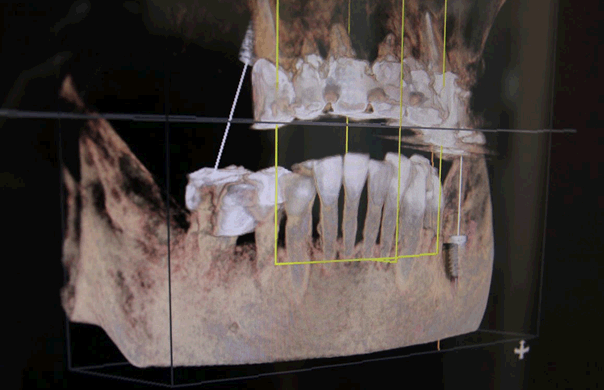

CTスキャンよる三次元映像により、骨の状態、神経の通っている位置を確認、さらに骨の質や密度を計算し、最適なインプラントを選択します。必然的に最も安全にインプラントを打つことのできる場所と角度が決まりますので、失敗なく手術することが可能です。

CTのデータを元に結果や神経を傷つけず安全にインプラントを埋入できる位置・深度を正確にシミュレーション可能です。

血管や神経を3次元で捉えることは、安全なインプラントに欠かせません。